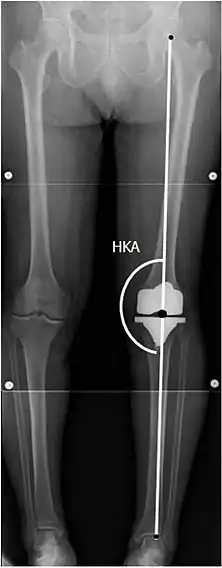

To indicate knee replacement in case of osteoarthritis, its radiographic classification and severity of symptoms both should be substantial. Such radiography should consist of weightbearing X-rays of both knees: AP, lateral, and 30 degrees of flexion. AP and lateral views may not show joint space narrowing, but the 30-degree flexion view is most sensitive for narrowing. Full-length projections also are used in order to adjust the prosthesis to provide a neutral angle for the distal lower extremity. Two angles used for this purpose are:

- Hip-knee-shaft angle (HKS),[9] an angle formed between a line through the longitudinal axis of the femoral shaft and its mechanical axis, which is a line from the center of the femoral head to the intercondylar notch of the distal femur.[11]

- Hip-knee-ankle angle (HKA),[10] which is an angle between the femoral mechanical axis and the center of the ankle joint.[11] It is normally between 1.0° and 1.5° of varus in adults.[12]